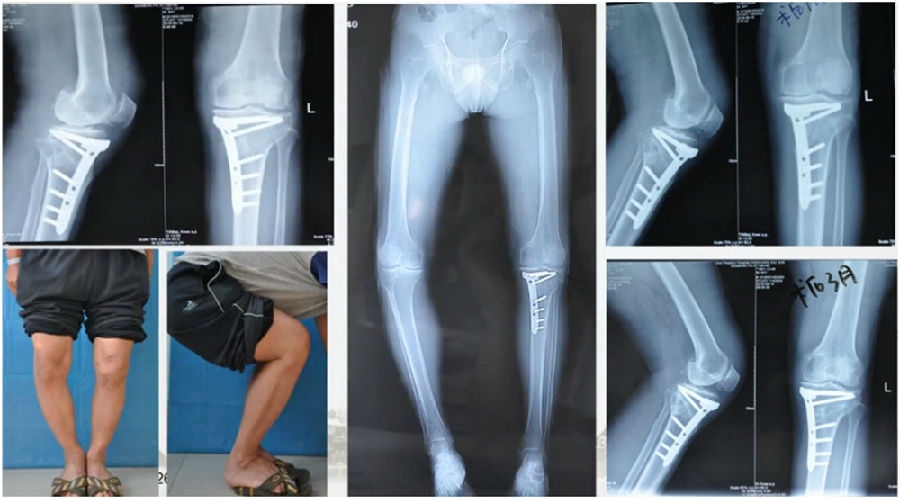

典型病例,女性,56岁,农民右膝内翻18度。

术前影像

术中影像

结合影像学来看,该患者单纯用闭合截骨或开放截骨,对肢体均有影响,所以决定采用混合型截骨。术中混合截骨旋转中心选在内外1/3处,先做闭合楔,然后顺势将开放楔敲开,达到术前设计的目标力线。术后随访力线达到要求。

术后X线